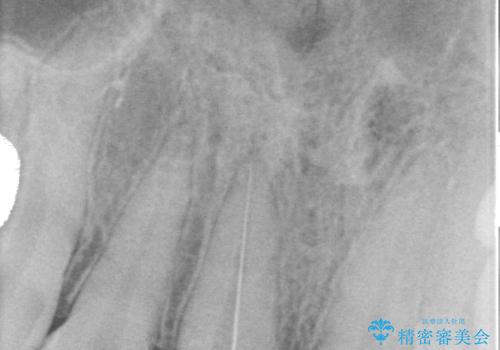

前歯に変色が起こる場合、神経組織の失活により引き起こる可能性が高いため、診察を行ったところ、根尖部の病変や叩いたときの痛みなどが認められました。

まずは根管治療を行い、痛みの消退を確認してからオールセラミッククラウンによる補綴治療を行うこととしました。

黄ばんできてしまった小臼歯部のクラウンは、根尖部に症状を認めないため、そのままオールセラミッククラウンによる補綴治療を行うこととしました。

前歯に痛みがあるという実感はなかったそうですが、診察で叩いたときの痛みを感じた際、今までに同様の痛みや違和感を感じたことがあったとのことでした。

初回の根管治療で痛みや違和感は消退したため、その後は速やかに補綴治療を行いました。